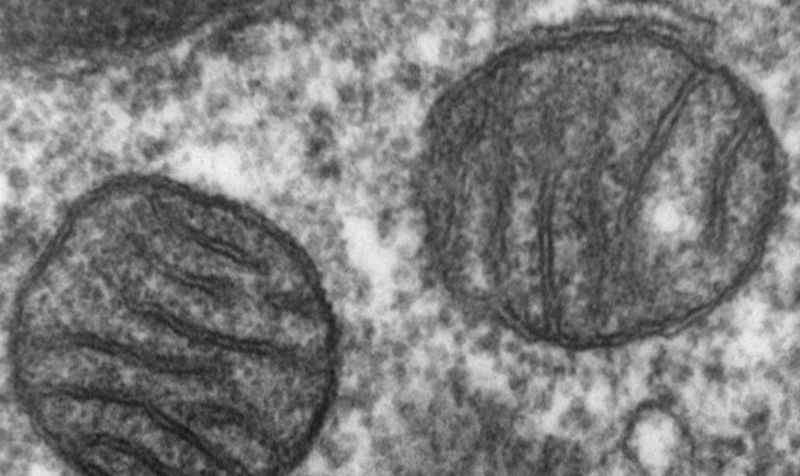

McCully studies heart damage prevention at Boston Children’s Hospital and Harvard Medical School and was keenly interested in mitochondria. These power-producing organelles are particularly important for organs like the heart that have high energy needs. McCully had been wondering whether transplanting healthy mitochondria into injured hearts might help restore their function.

Mitochondria are best known for producing usable energy for cells. But they also send molecular signals that help to keep the body in equilibrium and manage its immune and stress responses. Some types of cells may naturally donate healthy mitochondria to other cells in need, such as brain cells after a stroke, in a process called mitochondria transfer. So the idea that clinicians could boost this process by transplanting mitochondria to reinvigorate injured tissue made sense to some scientists.

From studies in rabbits and rat heart cells, McCully’s group has reported that the plasma membranes of cells engulf the mitochondria and shuttle them inside, where they fuse with the cell’s internal mitochondria. There, they seem to cause molecular changes that help recover heart function: When comparing blood- and oxygen-deprived pig hearts treated with mitochondria to ones receiving placebos, McCully’s group saw differences in gene activity and proteins that indicated less cell death and less inflammation.